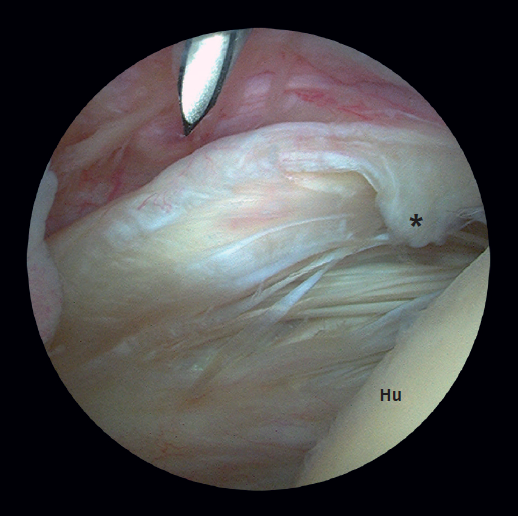

Figure 1. View from the posterior glenohumeral portal of a type IA (*) partial rupture of the subscapularis in a left shoulder not diagnosed by MRI. Hu: humerus.

The posterior lever push manoeuvre described by Burkhart(23) was used to the arm to improve the anterior space and allow better diagnosis and access to the lesion (Figure 1). The latter was explored by initially debriding the rotator interval as described by Lafosse(16), thus allowing better evaluation of frequent damage to the walls of the groove of the LPB, the stability of the LPB, and the size of SSC and SSP rupture(23). This exploration is made from the subacromial anterolateral approach, which allows much wider vision encompassing the entire coracoid space and the trajectory of the tendon.